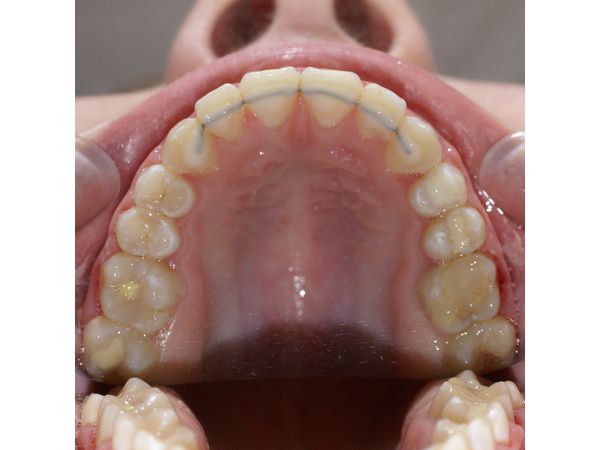

Пациентка была полностью удовлетворена результатом лечения. Ей также установили несъёмные ретейнеры Triple Flex с нёбной и язычной стороны зубов от клыка до клыка и назначили надевать на ночь съёмную капу на верхние зубы в течение полугода после того, как девушке сняли брекет-систему.

Нестандартная методика лечения ещё раз доказывает, что в ортодонтии нельзя использовать шаблонный подход. Каждый клинический случай необходимо рассматривать очень внимательно, стараясь не упустить ни одного нюанса, так как каждый из них может стать критическим при достижении желаемого результата.

В этом клиническом случае открытый прикус сопровождался скученностью зубов, при которой просто выровненные зубы открыли бы прикус ещё больше. Также в стандартной ситуации верхний ряд зубов держат на единой дуге, а нижний — на сегментарной, но в этом случае нижний зубной ряд был ближе к норме, поэтому необходимо было разделять только верхний ряд.